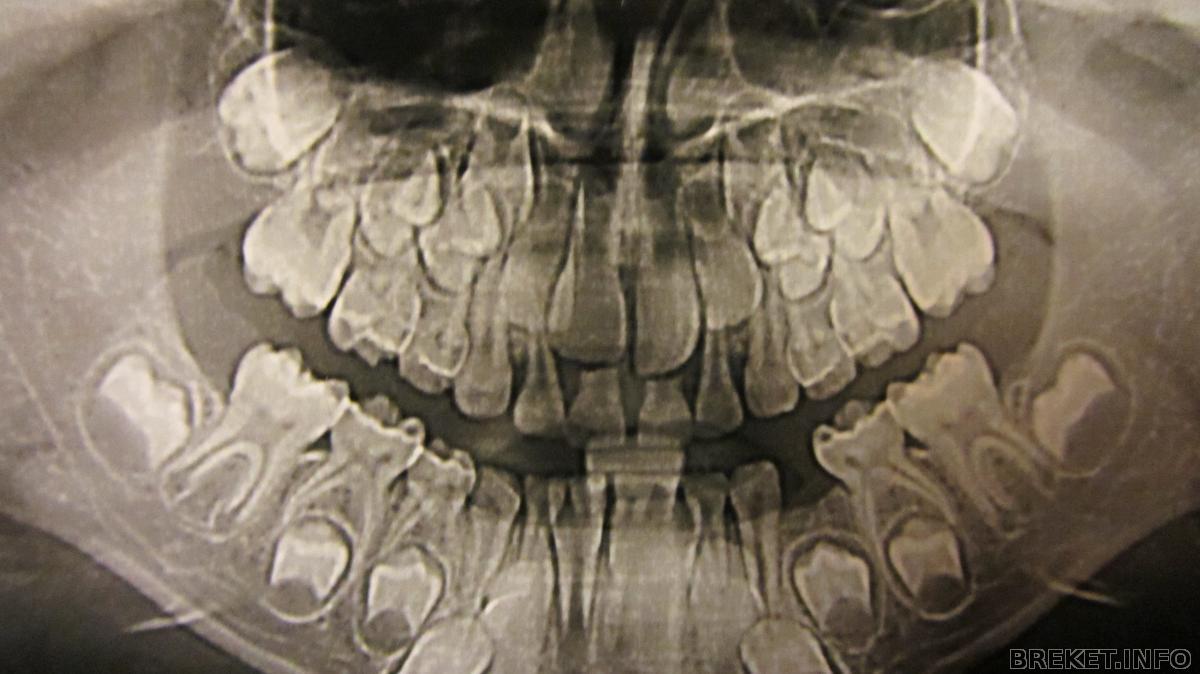

Сама была в шоке!!! детская челюсть

Это снимок моего сыночка . Ему 7 лет . Случайно совершенно заглянула ему в рот

и о Боги !!! Зубик вылез позади центрального резца ( единички )

) Говорит " Рвать , причем сразу два " Ну а что делать , зубы мои ! Мне 30 лет - 4 месяца назад вырвали последний молочный зуб. Воооот ! Сделали снимок . Я его разглядывала и диву давалась

Как однако все хитро устроенно в наших ртах. Зубы вырвали конечно ( это стоило мне игрушечного динозавра и машинки

у вас так здорово верхние стоят, готовые меняться!!!

наши где то совсем далеко сверху, а клыки вообще наискосок и прячутся за остальными, выше всех ( хотя уже 9 лет!